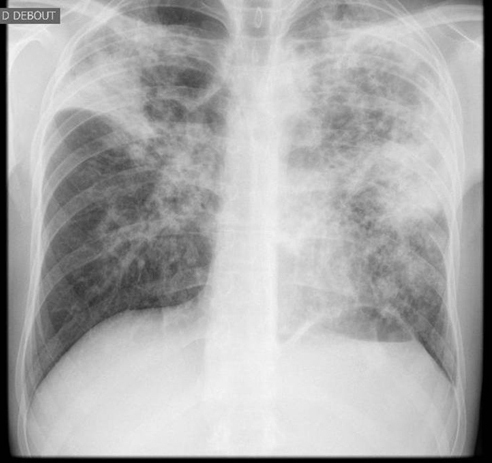

La Revue du Praticien - Hélène Leroy Radiographie thoracique. Lésions infiltratives bilatérales prédominant aux sommets, avec rétraction du sommet droit (déviation de la trachée).